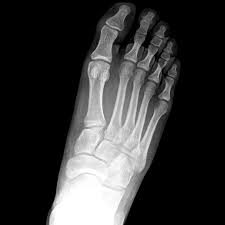

It is possible to sprain the lisfranc ligament, which does not require surgical intervention. A lisfranc injury, also known as a lisfranc fracture, happens when bones break or ligaments tear in the region in the middle of the feet. Sometimes, the injury is a simple dislocation (ligament injury), and sometimes a broken bone occurs. Partial ligament tears with no instability normal lisfranc. A lisfranc injury or lisfranc sprain is an injury to the ligaments in the middle part of the foot, called the midfoot.

Lisfranc injury is an important topic. What is a lisfranc injury? Lisfranc injuries in the athlete. Sometimes, the injury is a simple dislocation (ligament injury), and sometimes a broken bone occurs. It is possible to sprain the lisfranc ligament, which does not require surgical intervention. Recovery can be slow and painful. A lisfranc injury is an injury to the ligaments that connect the bones of the midfoot and forefoot. A lisfranc joint injury happens when you damage bones or connective tissue called ligaments in the middle part of your foot. The lisfranc joint complex, named for the french surgeon who first described it in the 1800s, includes the five metatarsal bones along with the tendons and ligaments. The midfoot section refers to the. The usual mechanism is a direct blow or an indirect twisting force the lisfranc joint complex consists of the 5 tarsometatarsal joints that connect the forefoot and midfoot. A lisfranc injury describes an injury of the foot between the metatarsal and tarsal spaces. A lisfranc injury happens when the ligaments or bones in the middle of your foot are fractured, sprained or dislocated.

Radiologists must have a thorough understanding of anatomy, mechanisms, and patterns of these injuries to diagnose and help. A lisfranc injury, also known as a lisfranc fracture, happens when bones break or ligaments tear in the region in the middle of the feet. A lisfranc injury occurs when one or more of the metatarsal bones are displaced from the tarsus, which is a cluster of bones at the top of the foot, just below the ankle joint. However, most athletes are able to successfully. Stable lisfranc injuries that do not require surgery may cause an athlete to miss 2 months or more of their season. Lisfranc injuries are a spectrum of injuries to the tarsometatarsal joint complex of the midfoot. Lisfranc injury or midfoot injury that result if bones in the midfoot are broken or ligaments that support the midfoot are torn. • medial edge of 2nd mt base should line up with the medial edge of middle cuneiform. A lisfranc injury or lisfranc sprain is an injury to the ligaments in the middle part of the foot, called the midfoot. Lisfranc injury indicates disruption between. Recovery can be slow and painful. It can occur in one or both feet. Ebraheim's animated educational video describing lisfranc injury.